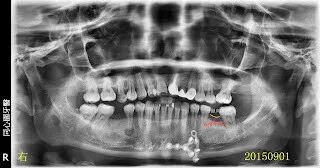

假牙材質2臨床案例...不同的假牙材質+牙齦萎縮